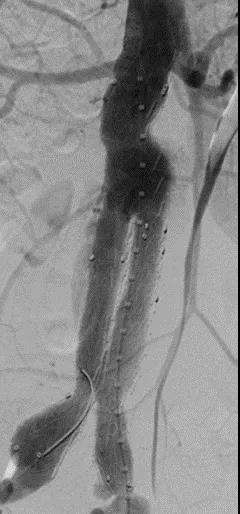

此次研究,纳入腹主动脉瘤的最大直径为85mm,平均直径为50.78mm;最短瘤颈长度为11mm,平均长度为31.34mm;最大肾下成角为74.6度,平均角度为32.48度。从动脉瘤最大直径变化来看,经过腹主动脉腔内治疗后,在出院前和术后6个月都有所减小。 在此次研究中,彩神在线网信彩票-彩神通免费版下载-彩神8争霸vlll-彩神购彩购彩大厅-彩神软件陆立根免费版-彩神ll争霸3-彩神ll彩神8-彩神ll争霸彩票-拼搏在线彩神网网页版Yuranos™新一代腹主动脉覆膜支架系统临床试验初步展现了优秀的临床试验结果,其30天内MAE发生率低,安全性得以验证;而且由于该产品的柔顺性有较大提升,输送器直径减小,对于短瘤颈和角度大的病例是更好的选择。 入组病例展示: 病例一:男性,年龄69岁,既往高血压,糖尿病病史。术前腹主动脉瘤直径67.3mm,近端瘤颈长度23.2mm,近端锚定区直径21.2mm,肾下成角60.5度。 术中从右侧股动脉穿刺,选用彩神在线网信彩票-彩神通免费版下载-彩神8争霸vlll-彩神购彩购彩大厅-彩神软件陆立根免费版-彩神ll争霸3-彩神ll彩神8-彩神ll争霸彩票-拼搏在线彩神网网页版型号为AB-2412-50-120的主体支架,支架近端定位于右肾动脉开口处,后释放打开裸支架,并向下释放主体短分支,左侧输送进入彩神在线网信彩票-彩神通免费版下载-彩神8争霸vlll-彩神购彩购彩大厅-彩神软件陆立根免费版-彩神ll争霸3-彩神ll彩神8-彩神ll争霸彩票-拼搏在线彩神网网页版髂动脉延长支架IE-1416-100,并释放,保留左侧髂内动脉。接着释放主体长分支,右侧输送进入彩神在线网信彩票-彩神通免费版下载-彩神8争霸vlll-彩神购彩购彩大厅-彩神软件陆立根免费版-彩神ll争霸3-彩神ll彩神8-彩神ll争霸彩票-拼搏在线彩神网网页版髂动脉延长支架IE-1424-80,并释放,保留右侧髂内动脉。 手术顺利,无内漏,持续时间1小时10分钟。术后CTA检查,支架形态良好,无内漏。详见下图: 术前影像 术中影像 出院前影像 术后6个月影像 术后1年影像 病例二:女性,年龄72岁,既往高血压,静脉曲张病史。术前腹主动脉瘤直径48.81mm,近端瘤颈长度16.15mm,近端锚定区直径18.43mm,肾下成角66度。 术中从右侧股动脉穿刺,选用彩神在线网信彩票-彩神通免费版下载-彩神8争霸vlll-彩神购彩购彩大厅-彩神软件陆立根免费版-彩神ll争霸3-彩神ll彩神8-彩神ll争霸彩票-拼搏在线彩神网网页版型号为AB-2412-50-140的主体支架,支架近端定位于右肾动脉开口处,后释放打开裸支架,并向下释放主体短分支,左侧输送进入彩神在线网信彩票-彩神通免费版下载-彩神8争霸vlll-彩神购彩购彩大厅-彩神软件陆立根免费版-彩神ll争霸3-彩神ll彩神8-彩神ll争霸彩票-拼搏在线彩神网网页版髂动脉延长支架IE-1414-120,并释放,保留左侧髂内动脉。接着释放主体长分支,右侧输送进入彩神在线网信彩票-彩神通免费版下载-彩神8争霸vlll-彩神购彩购彩大厅-彩神软件陆立根免费版-彩神ll争霸3-彩神ll彩神8-彩神ll争霸彩票-拼搏在线彩神网网页版髂动脉延长支架IE-1414-80,并释放,保留右侧髂内动脉。